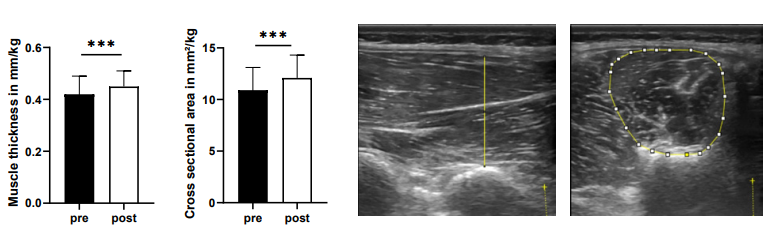

Die tiefliegenden Rückenmuskeln, oftmals auch als autochthon („ortsständig“) bezeichnet, haben eine Schlüsselfunktion bei der Aufrichtung und Stabilisierung der Wirbelsäule [Wagner et al., 2005]. Vor allem die Muskeln des sogenannten „medialen Stranges“ sind segmental angeordnet und daher für die segmentale Stabilisierung und Hauptkontrolle der Wirbelsäule verantwortlich (siehe Abb. 1) [Creze et al., 2015; Deng et al. 2015]. Unterstützt werden diese Muskeln von einem komplexen System aus Faszien. Gut trainierte Muskeln erhöhen diese fasziale Spannung und gewährleisten eine systemische Stabilität [Willard et al., 2012].

Abb.1: Lateraler (links) und medialer (rechts) Strang der autochthonen Rückenmuskulatur